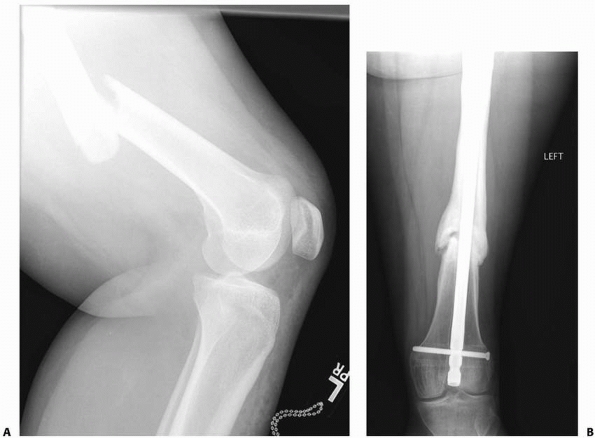

![]() |

FIGURE 22-20 AP (A) and lateral (B)

x-rays a low-energy short oblique fracture through a fibrous cortical defect in the distal femur; this type of fracture is not unusual. The surgeon judged that there was enough distance between the fracture site and the growth plate to allow external fixation. AP (C) and lateral (D) x-rays 3 weeks after external fixation shows early callus and good alignment. The external fixation was removed shortly after this x-ray and the child was placed in a long leg cast, with weight bearing as tolerated. |